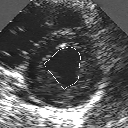

DETECTION AND TRACKING OF ANATOMICAL STRUCTURES USING DEFORMABLE TEMPLATES AND A NOISE MODEL ESTIMATION IN AN ECHOGRAPHIC SEQUENCE

In this work, we present a new method to shape-based segmentation of deformable anatomical structures in medical images and validate this approach by detecting and tracking the endocardial border in an echographic image sequence. To this end, a global prior knowledge of the endocardial contour is captured by a prototype template with a set of admissible deformations to take into account its inherent natural variability over time. In this approach, the data likelihood model rely on an accurate statistical modeling of the grey level distribution of each class present in the image. The parameters of this distribution mixture are given by a preliminary estimation step which takes into account the distribution shape of each class. Then the tracking problem is stated in a Bayesian framework where it ends up as an optimization problem. This one is then efficiently solved by a genetic algorithm combined with a steepest ascent procedure. This technique has been successfully applied on synthetic images and on a real echocardiographic image sequence. This method seems to be particularly well suited to handle ultrasound images with strong speckle noise on which edge information cannot be exploited. Finally, the local and global minimization procedure we propose is fast, robust and do not require initialization of the template close to the desired solution. Initialization may be defined at random, leading to segmentation and tracking procedure that are completely data driven. (slides)

Figure 1:   Tracking of the endocardial contour in a medical echographic sequence at different time frames during the cardiac cycle. From top left to bottom right : frame 1, 4, 6, 9, 12, 13, 18, 20, 27, 30, 35, 40, 41, 44, 46.